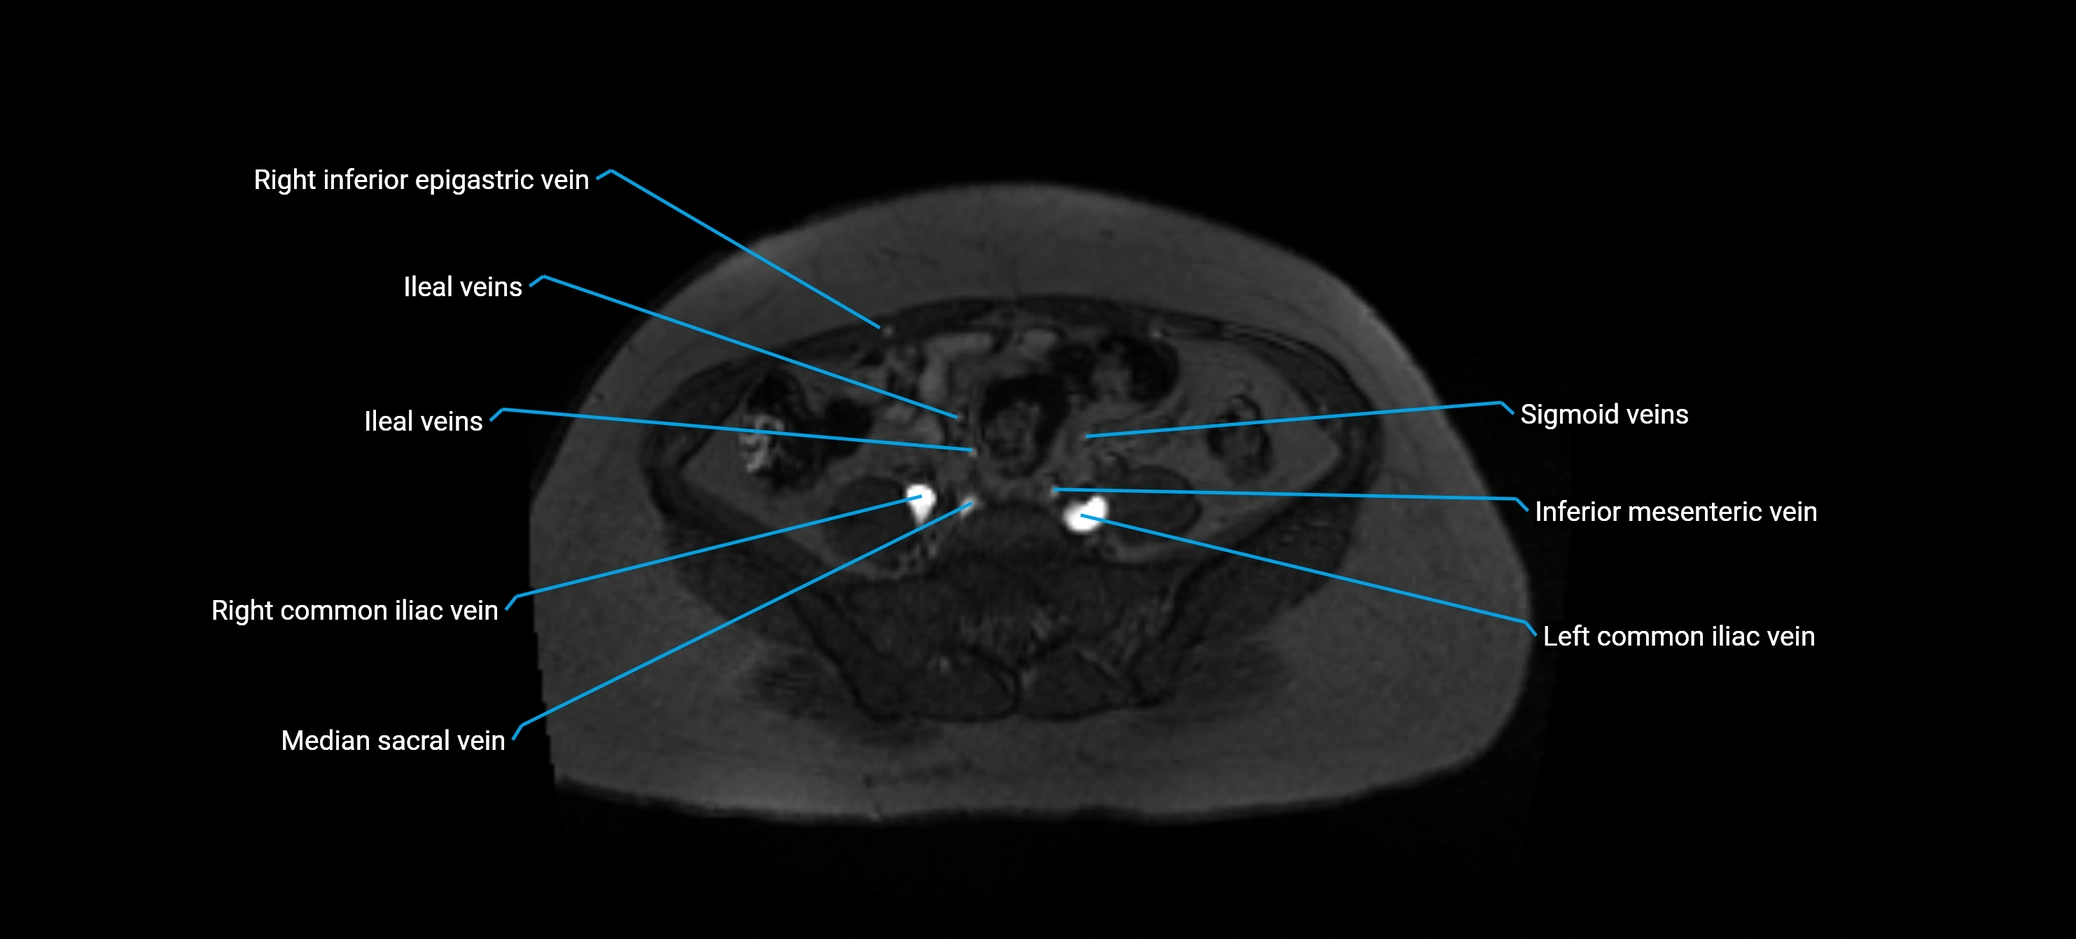

MRI image

image